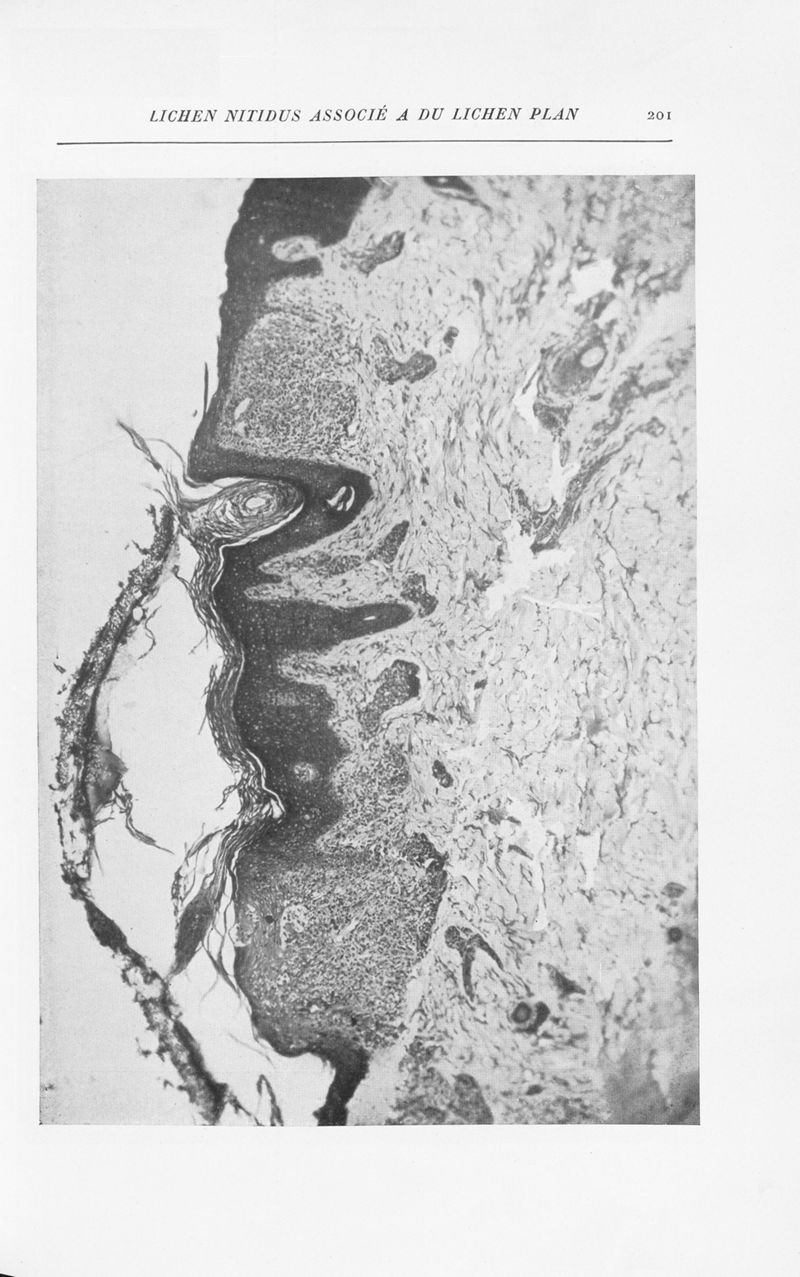

Annales de dermatologie et de syphiligraphie

7ème série, tome VIII. - Paris : Masson, 1937.